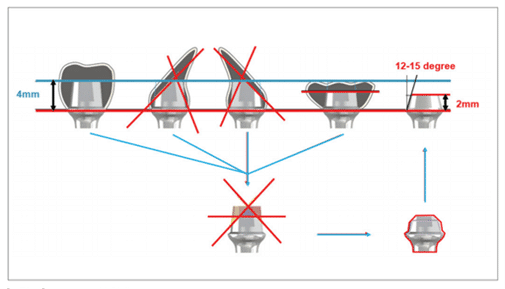

Le Magic Post est une structure située au sommet du MagiCore. Il améliore la polyvalence des prothèses des implants de niveau tissulaire et permet une implantation au centre de l’os de la mâchoire (ostéo-centrée).

Lors de l’installation d’un implant bone level en deux parties au niveau de l’os avec la connexion interne largement utilisée, il est nécessaire d’aligner la direction des forces occlusales avec l’axe longitudinal de l’implant afin d’éviter les fractures de l’implant. Dans certains cas, pour aligner ces deux directions, une intervention chirurgicale plus invasive au niveau de la prothèse peut être nécessaire pour adapter la forme finale de la prothèse.

En revanche, le MagiCore évite le désalignement de la prothèse, même dans les situations où il existe une grande différence entre la direction des forces occlusales et l’axe longitudinal de l’implant, grâce à la double connexion solide fournie par le Magic Post (figures 13, 14).

(Figures 13) Utilisation du MagiCore dans les cas où il y a une importante disparité entre la direction des forces occlusales et l’axe longitudinal de l’implant lors de sa pose.

(Figures 14) Utilisation du MagiCore dans les cas où il y a une importante disparité entre la direction des forces occlusales et l’axe longitudinal de l’implant lors de sa pose.

De plus, grâce aux caractéristiques du Magic Fin Thread mentionnées précédemment, il peut augmenter la résistance aux forces de cisaillement.

Le Magic Post est conçu avec des connexions externes et internes, offrant un espace de 2 mm pour obtenir l’effet de ferrule à l’extérieur et un espace de 4 mm pour obtenir une connexion interne solide.

Cela permet d’obtenir une double connexion robuste, prévenant le détachement vertical et rotatif de la prothèse. De plus, elle contribue à disperser les forces lors de l’application des forces occlusales, réduisant ainsi considérablement le risque de fracture de l’implant (figure 15).

En effet, la hauteur de 2 mm du Magic Post joue un rôle crucial dans l’obtention d’une polyvalence dans la fabrication prothétique. Grâce à sa faible hauteur de 2 mm et à son angle externe incliné, il peut s’adapter à une variété de techniques prothétiques implantaires basées sur la dentisterie implantaire moderne (figures 16, 17).